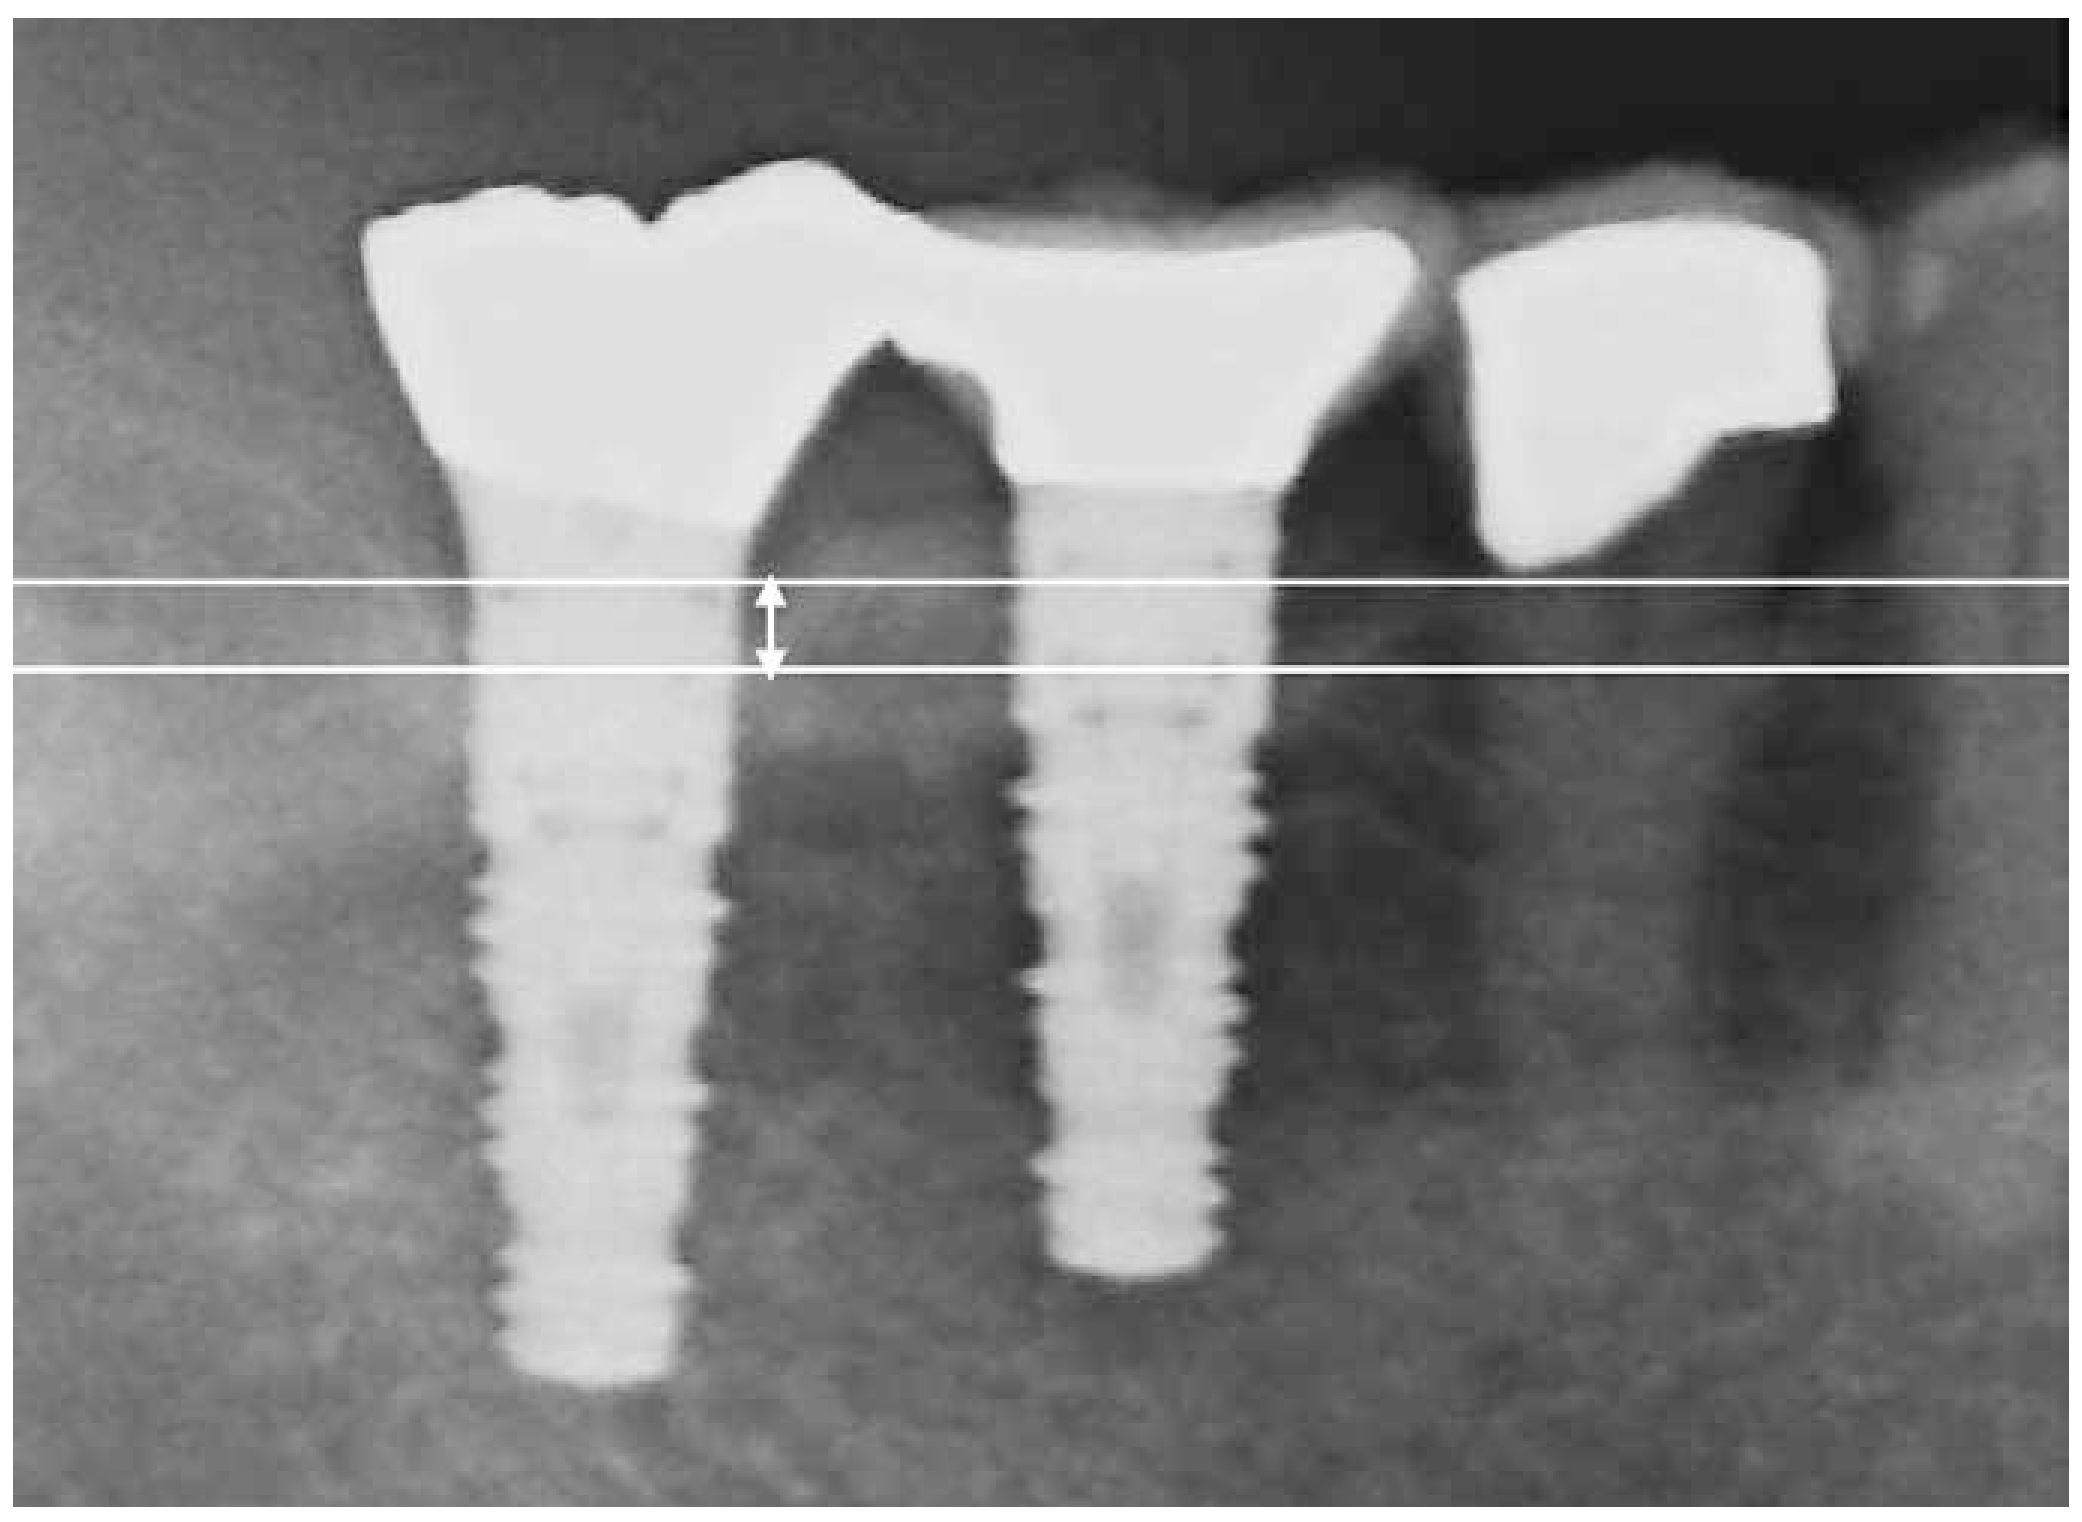

Radiographic images were acquired using either a dental X-ray unit with a long-cone paralleling technique or a panoramic radiograph. Bone volume was calculated by measuring the distance from the marginal bone level to the implant apex (a), and the implant length (b). The ratio of (b/a) was used to estimate relative bone volume. Baseline bone volume was defined as the radiographic measurement taken one year after prosthetic loading. The difference between baseline and current bone volume was defined as marginal bone loss.7,8 (Figure 1: Criterion 1). Alternatively, as Criterion 2, the vertical distance from the marginal bone crest to the base of the intrabony defect was measured as the bone defect depth (Figure 2: length of white arrow).

Fig 1

(Fig.1) Criterion 1

Fig 2

(Fig.2) Criterion 2.The white arrow indicates the amount of bone loss, defined as the distance from the bone crest to the base of the bone defect.